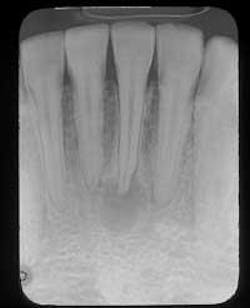

A 27-year-old male visited a dental office for a checkup and prophy. Radiographic examination revealed a radiolucency around the apex of tooth #24.

Examination of the head and neck region revealed no palpable lymph nodes. All vital signs were found to be within normal limits. Oral examination revealed no soft tissue or bony abnormalities. Radiographic examination re-vealed a well-defined radiolucency around the apex of tooth #24 (see film). The mandibular anterior teeth were tested for vitality; teeth #22, 23, 25, 26, and 27 all tested vital while tooth #24 tested nonvital.

There are no distinctive radiographic differences between a radicular cyst, a periapical granuloma, and a periapical abscess. The size and appearance of the borders (corticated vs. noncorticated) are not diagnostic. The typical periapical cyst appears as a round to ovoid radiolucency. The size may range from less than 1/2 centimeter to several centimeters in diameter. The borders may be corticated or noncorticated. Root resorption may be seen.